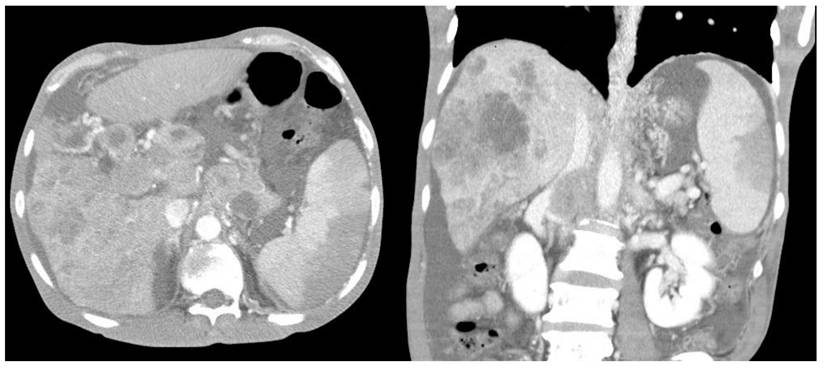

Furthermore, compared with survivors, the non-survivors exhibited significantly higher rates of left-sided pleural effusion, peri-splenic ascites, multiple or total infarction, main portal vein thrombosis, and splenic vein thrombosis on CT imaging. Co-infarctions most commonly involved the kidneys, brain, and intestines. At least one organ co-infarction occurred in 30.6% of cases, while 11.5% experienced two or more, but no significant group differences were observed (Table S4). Figure 2 shows concurrent splenic and left renal infarction, whereas Figure 3 shows splenic infarction with portal vein thrombosis and ascites in a patient with hepatocellular carcinoma.

Figure 2

Concurrent splenic and left renal infarction. Contrast-enhanced abdominal CT images showing wedge-shaped hypodense regions within the spleen on the axial view (left panel) and within both the spleen and the left kidney on the coronal view (right panel).